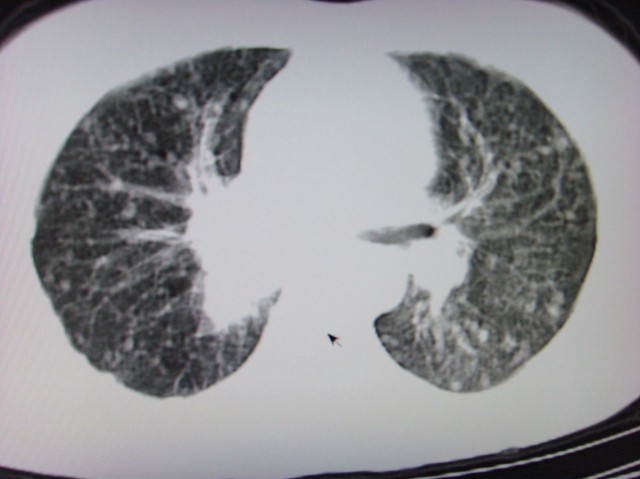

标题: CT7125:中央性肺Ca.

典型 中央型ca伴双肺、淋巴结转移

右下中心型肺癌伴双肺转移、纵隔淋巴结转移,癌性淋巴管炎可能性大

典型--右下中心型肺癌伴双肺转移、纵隔淋巴结转移,癌性淋巴管炎可能性大

中心型肺癌伴双肺转移及纵隔淋巴结转移,癌性淋巴管炎

典型的中央型ca,肿快和肺门分界不清,肿快边界模糊,呈毛刺状。伴淋巴结转移。